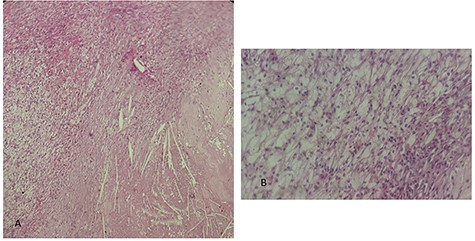

This is a 50-year-old patient with a history of medically treated renal lithiasis, who consults for left low back pain. The patient was apyretic and reported no urinary symptoms. The clinical examination was without any particularities. There was no organomegaly or lumbar contact on bimanual palpation. Biologically, there were no abnormalities, including no biological inflammatory syndrome, and renal function was preserved. The urine culture was sterile. Renal ultrasound revealed a 3-cm left cortical renal mass with moderate vascuarization. Abdominal CT scan confirmed the presence of a heterogeneous Bosniak type 3 cystic mass having a thickened wall (Fig. 1). Abdominal MRI showed a left polar cyst having an exophytic development and a thickened wall with spontaneous T2 hypointensity and T1 hyperintensity without any pathological enhancement after Gadolinium injection (Fig. 2). The retained diagnosis was an hemorrhagic benign cyst. At multidisciplinary meeting, the decision was to perform an MRI 3 months later which showed a left medio-renal cortical cystic mass measuring 24 × 28 mm having a T1 hyperintensity and heterogeneous T2 hypointensity, with a thickened wall mildly enhanced after contrast injection evoking a Bosniak type-3 hemorrhagic cyst. Seeing the MRI results, we decided to perform a left tumorectomy. Pre-operatively, the perirenal tissues were inflammatory and adherent to the capsule, a complete dissection of the kidney was performed allowing the identification of the tumor which was of a 3-cm diameter and a partially exophyctic development, then we cut the tumor with a 2-mm surgical margin. No urinary tract leakage was observed. Finally, renorraphy was performed in two plans using Vicryl 2-0 and 1 (Ethicon, Cincinnati, OH, USA). After confirming the lack of active bleeding, we placed a drainage tube and closed the incision. The total operation time was 1 h 45 min, with 18 min of selective clamping. The post-operative course was uneventful, and the patient was discharged 2 days post-operatively. The histopathological examination revealed a 2.5 × 2.7 cm necrotic lesion with an inflammatory interstitial infiltrate dissociating the epithelial structures (Fig. 3). The retained diagnosis was a pseudo tumoral Xanthogranulomatous pyelonephritis. The CT performed 3-months after surgery showed no abnormalities.

histological examination. (A) Hematoxylin Eosin × 20: inflammatory granulomatous changes in contact with cholesterol crystals. (B) Hematoxylin Eosin × 40: inflammatory infiltrate rich in xanthemous foam cells.